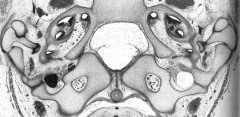

Transverse section through the base of the skull